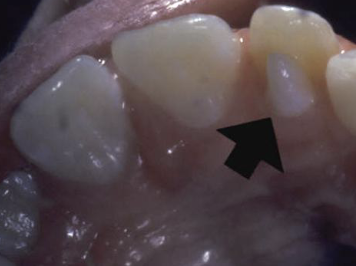

enamel nodules at furcation of multi-rooted teeth, most common in max molars, may have pulp tissue usually without dentin

enamel pearl